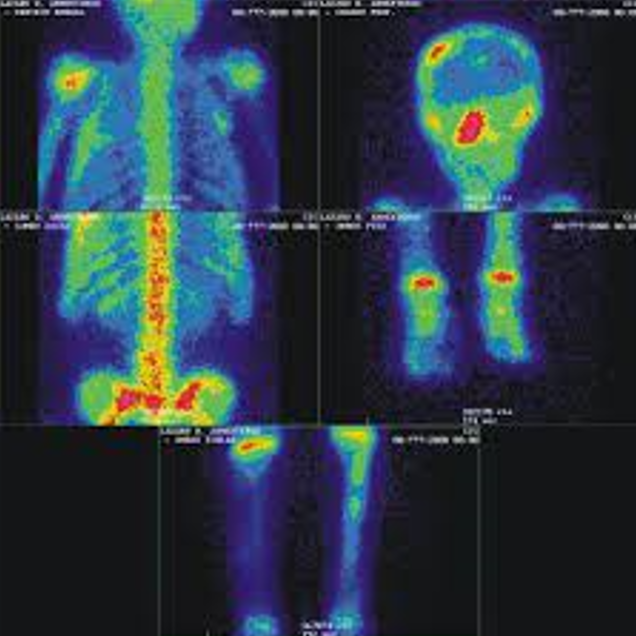

Una gammagrafía ósea implica inyectar una cantidad muy pequeña de material radiactivo (marcador) dentro de una vena. La sustancia viaja a través de la sangre hasta los huesos y órganos. A medida que esta va desapareciendo, emite un poco de radiación. Esta es detectada por una cámara que lentamente escanea el cuerpo.

Toma imágenes del marcador que hay en sus huesos. El técnico puede solicitarle que cambie de posición durante el procedimiento. Esto ayuda a obtener imágenes desde diferentes ángulos. Una gammagrafía ósea de todo el cuerpo tarda aproximadamente 1 hora en completarse.

La cámara gamma detecta las emisiones de energía de la radiosonda en su cuerpo y las convierte en una imágen. La cámara gamma de por sí no emite ninguna radiación. Tiene detectores de radiación denominados cabezas de cámara gamma.